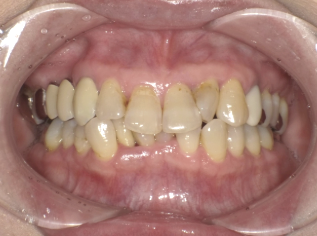

Before Photo

Before